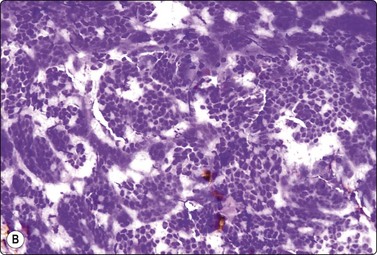

Neuroblastoma (see Chapter 17)

The cytology of neuroblastoma, ganglioneuroblastoma and ganglioneuroma seen in FNB smears is described in Chapter 17, where several references are also given. The pattern is basically of a malignant small round cell tumor common to a range of neoplasms including small cell anaplastic carcinoma, Wilms’ tumor, embryonal rhabdomyosarcoma, etc. Characteristic rosettes of tumor cells, in the center of which there is finely fibrillar, pink staining (MGG) material (neuropil), are often found but are not specific (Fig. 12.38). As with other malignant small round cell tumors, a type-specific diagnosis should be supported by immunocytochemical, ultrastructural or other ancillary studies, which can be carried out on FNB samples (see p. 428).

image image

Fig. 12.38 Neuroblastoma

(A) Cell-rich smear; small round cell pattern with a suggestion of rosettes and a small amount of fibrillar intercellular material; irregular hyperchromatic nuclei (MGG, HP); (B) Corresponding tissue section showing some rosettes with neuropil (H&E, HP).